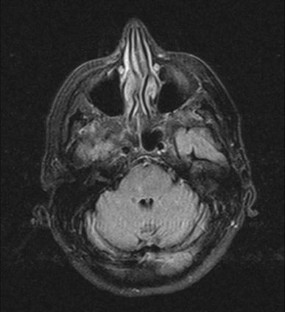

Fig. 1

Isolated paresthesia, or paresthesia not accompanied by sensory and/or motor deficits, is an extremely rare manifestation of a cerebrovascular accident. Lacunar pure sensory stroke (PSS) confined to thalamus is characterized by persistent or transient numbness, tingling, pain, burning, or another unpleasant sensation on one side of the body. However, in this condition a sensory loss to all primary modalities in the contralateral face and body is very often encountered. Also previous reported cases of PSS due to lacunar stroke in regions other than thalamus are characterized by the presence of sensory loss together with positive sensory symptoms, none of them reporting isolated paresthesia as the only clinical feature of PSS. We present a case of isolated paresthesia as only clinical manifestation of a lacunar PSS involving both trigeminal and medial lemniscus in dorsal paramedian pontine region. A PSS manifesting with isolated paresthesias may be secondary not only to a thalamic lacunar stroke, but also to a small ischemic lesion confined to both trigeminal and medial lemniscus in dorsal paramedian pontine region.